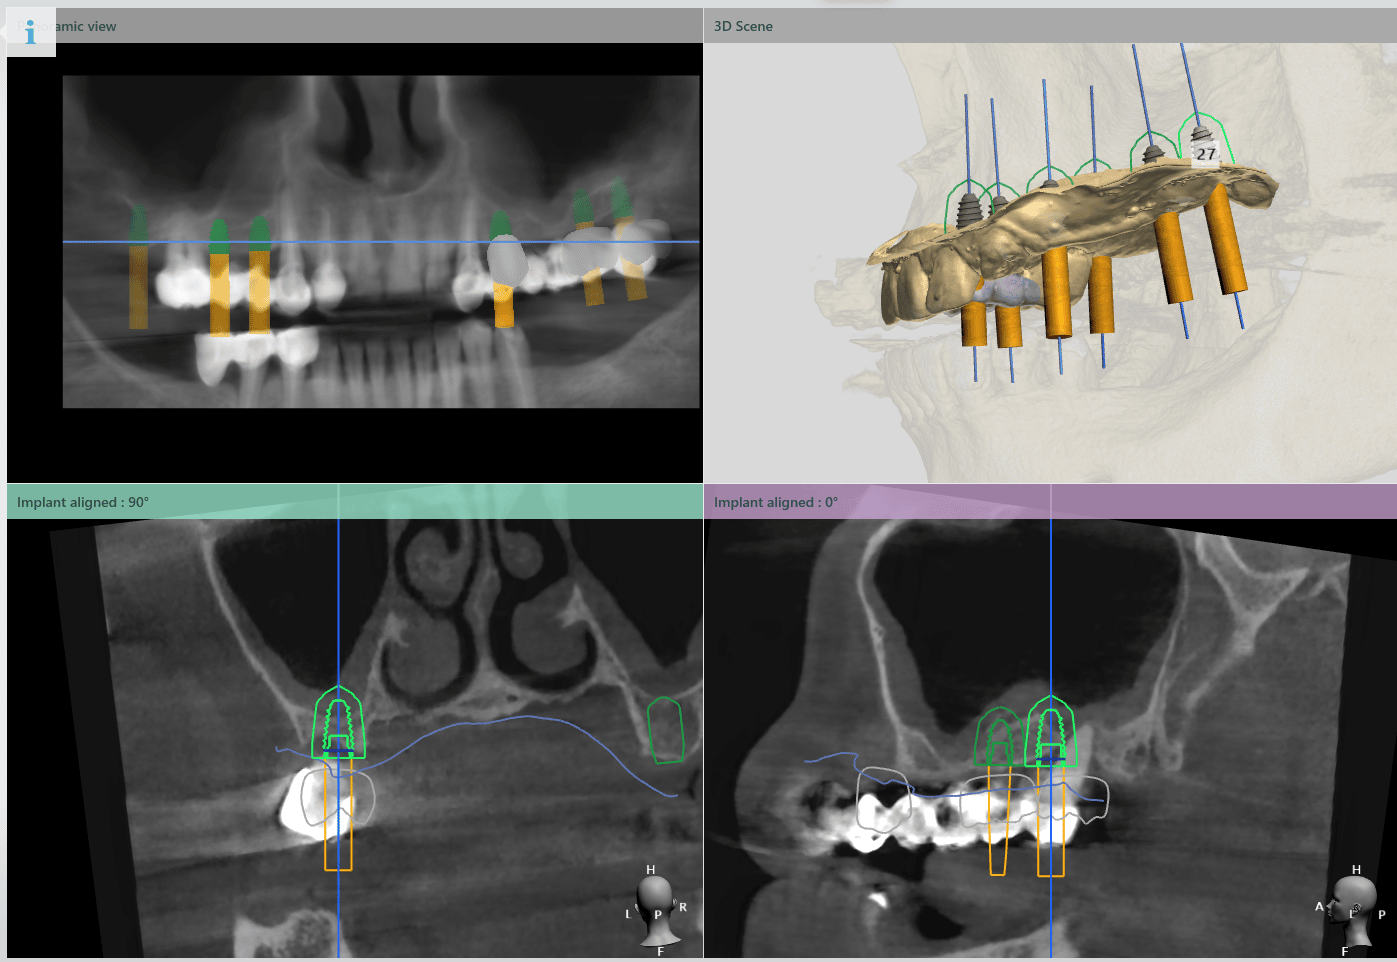

Planul inițial a fost extracția dinților 16 și 28 și inserarea implanturilor în pozițiile 14, 15, 17, 24, 26, 27.

În urma evaluării CBCT-ului s-a constatat necesitatea realizării augmentarii osoase ăn zona posterioară maxilară, lifting sinusal maxilar bilateral odată cu inserarea implanturilor.

De asemenea s-au planificat implanturi în pozițiile 46, 47, 36, 37.

Pentru a se asigura că implanturile dentare vor fi plasate în poziția ideală din punct de vedere estetic și funcțional, medical implantolog a recomandat inserarea implanturilor dentare cu ajutorul ghidului chirurgical.

Medicul specialist a efactuat scanarea digitală a arcadelor pe care a trimis-o tehnicianului dentar DigiRay, împreună cu CBCT-ul pacientului.

Odată planficată și agreată poziția și axul de inserție al fiecarui implant, tehnicianul DigiRay efectuează designul șablonului chirurgical și printarea acestuia dintr-o rășină bio-compatibilă.